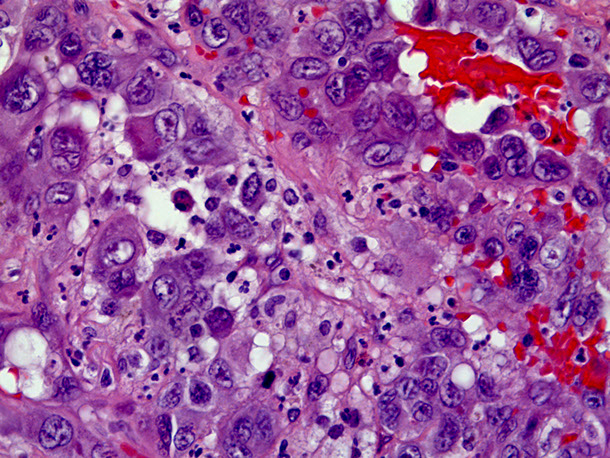

Angiosarcoma

Bland-appearing angiosarcoma with multilayered endotheliom that infiltrates (splits) through collagen

Angiosarcoma can have more solid, spindly areas

C, Epithelioid angiosarcoma demonstrates focal vasoformative features. The tumor is diffusely positive for CD31 (D) and Friend leukemia integration 1 transcription factor (FLI1) (E), with a variable CD34 expression (F) (hematoxylin-eosin; original magnification x20 [D through F]).

Rare tumor in adults, (<1% of sarcomas), ~7th decade (very rare in kiddos) derived from endothelial cells of blood vessels that can occur in multiple sites depending on type of risk factor exposure

Micro: atypical vascular spaced lined by endothelial cells c atypia and multilayering that involves subQ and has RBCs in intracytoplasmic lumina in more solid areas

- lots of mits and necrosis

IHC: (+) Factor 8 related peptide, CD31, Ki-67, FLI-1, thrombomodulin, CD34, c-kit, VEGFR-3, ERG, INI-1 (is lost in epithelioid sarcoma)